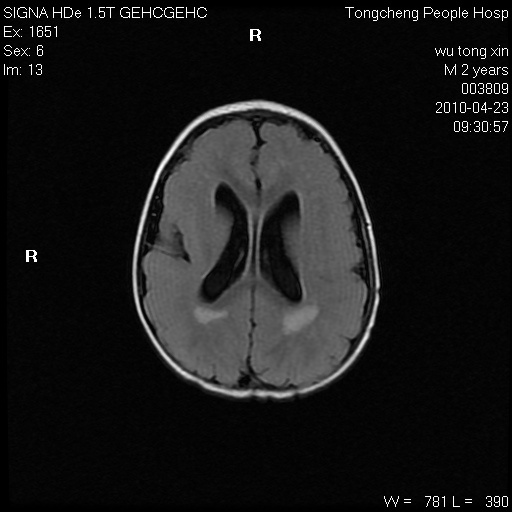

以下是引用赵物学在2010-4-25 12:43:00的发言:[br]巨脑回[br]侧脑室后角低密度影考虑hie或肾上腺脑白质营养不良?[br][br][本贴已被 赵物学 于 2010-4-25 12:51:28 修改过]

以下是引用gaoxiao在2010-4-25 16:54:00的发言:[br]巨脑回畸形。脑白质髓鞘化不良

以下是引用pujunzhi在2010-4-25 21:35:00的发言:[br]考虑 1双侧大脑皮质发育不良 2轻度脑积水 3双侧脑室后角旁片状长t1长t2信号,需继续观察,因为正常小儿此处脑白质的髓鞘化时间可以延迟到4-6岁,才显示正常。